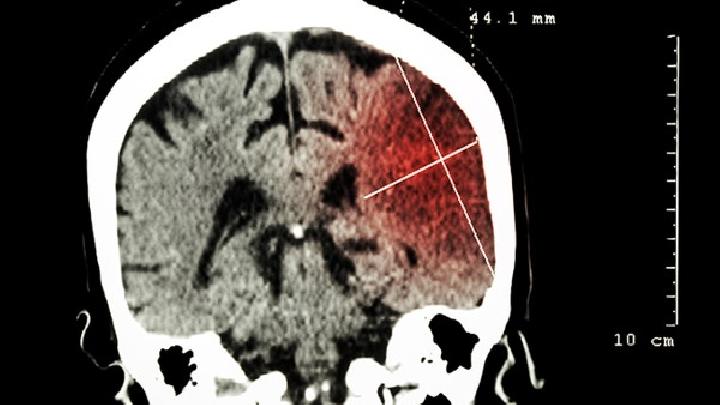

1、姿势异常:受异常肌张力和原始反射消失不同情况影响,患者可出现多种肢体异常姿势,并因此影响其正常运动功能的发挥。体检中将患者分别置于俯卧位、仰卧位、直立位、以及由仰卧牵拉成坐位时,即可发现瘫痪肢体的异常姿势和非正常体位。下肢股部明显内收,两膝紧紧靠拢,行走时呈剪刀或交叉步态,足部呈马蹄畸形,多以足尖着地,步态雀跃不稳,甚至步行困难。

2、运动系统异常表现:临床症状:运动发育落后和瘫痪肢体主动运动减少,不能完成相同年龄正常小儿应有的运动发育进程,包括竖颈、坐、站立、独走等粗大运动,以及手指的精细动作。

3、反射异常:多种原始反射消失延迟。痉挛型脑瘫患者腱反射活跃,可引出踝阵挛和阳性Babinski征。

4、肌张力异常:因不同临床类型而异,痉挛型表现为肌张力增高,肌张力低下型则表现为瘫痪肢体松软,但仍可引出腱反射;而手足徐动型表现为变异性肌张力不全。少数病人有面肌痉挛,也中有不自主手足徐动。